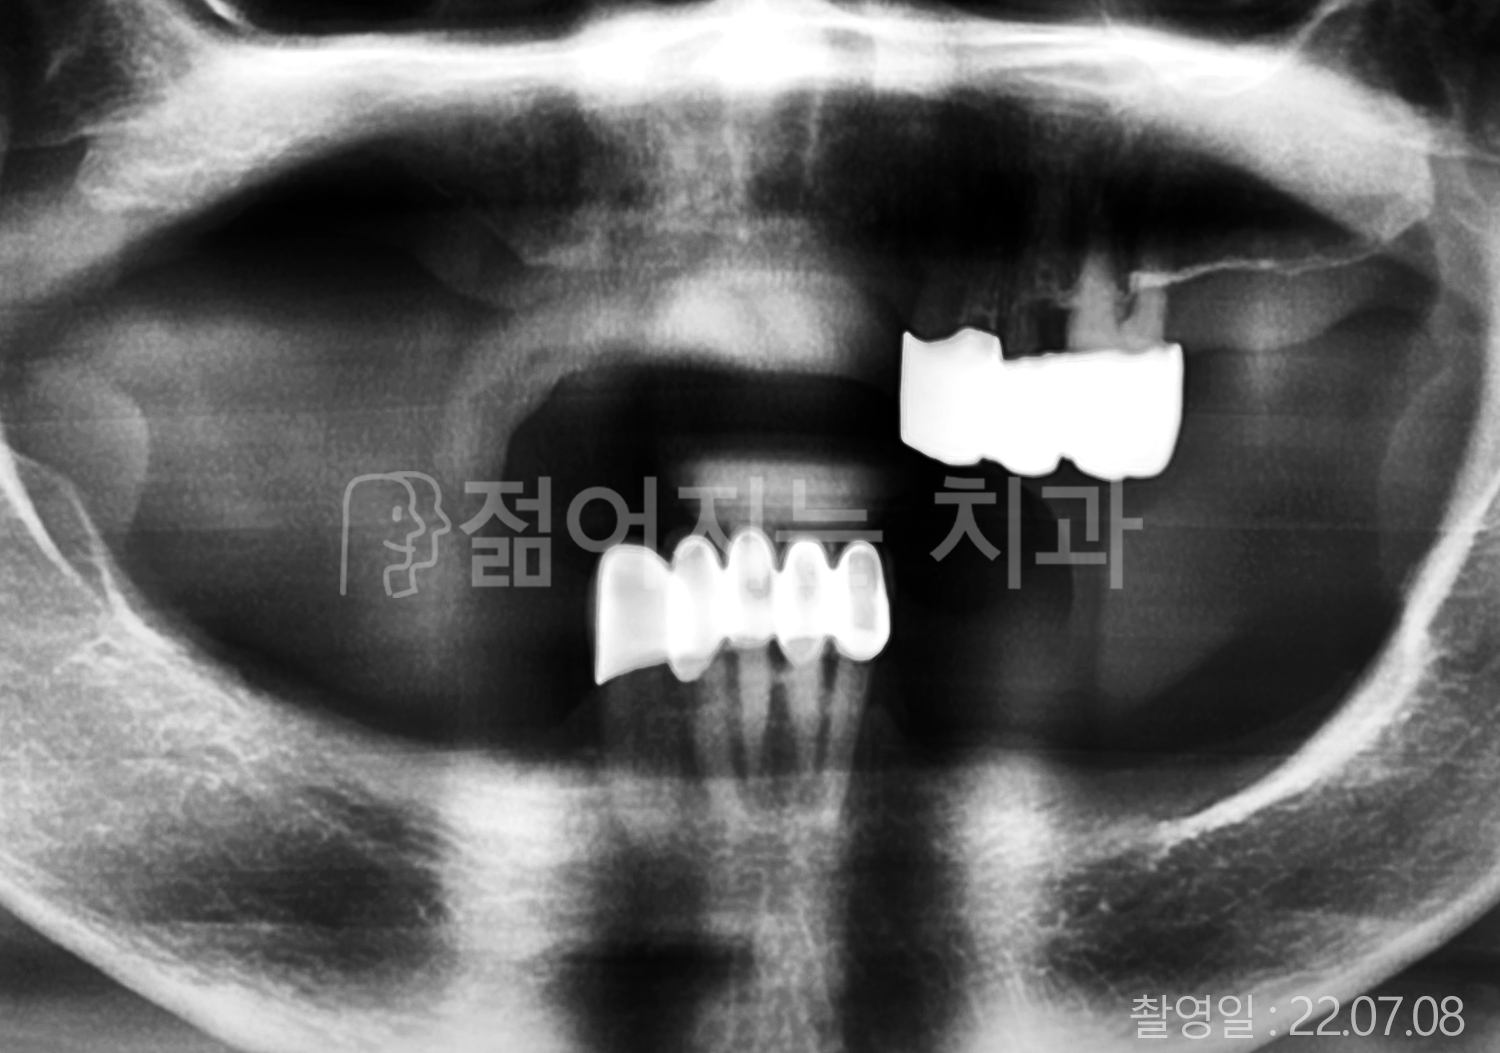

• 50대 고혈압, 당뇨, 고지혈증 전체치아 10개 이상 임플란트

• 60대 골다골증, 간경화 전체치아 10개 이상 임플란트

• 60대 고혈압, 고지혈증 전체치아 10개 이상 임플란트

• 50대 고혈압, 당뇨 전체치아 10개 이상 임플란트

• 60대 고혈압 전체치아 10개 이상 임플란트

• 60대 전체치아 10개 이상 임플란트

• 60대 고지혈증 전체치아 10개 이상 임플란트

• 40대 전체치아 10개 이상 임플란트

• 70대 전체치아 10개 이상 임플란트